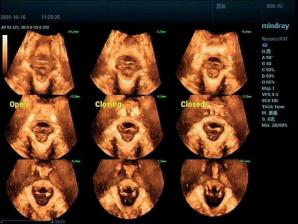

关注盆底健康,为女性保驾护航

除了孕期服务,科室还为女性盆底健康提供专业评估。三维超声可清晰呈现盆底肌肉、韧带等支撑结构,精准测量肛提肌裂孔面积等关键指标,帮助医生早期发现压力性尿失禁、盆腔器官脱垂等问题,为后续康复方案制定与手术评估提供科学参考,守护女性产后及长期健康。